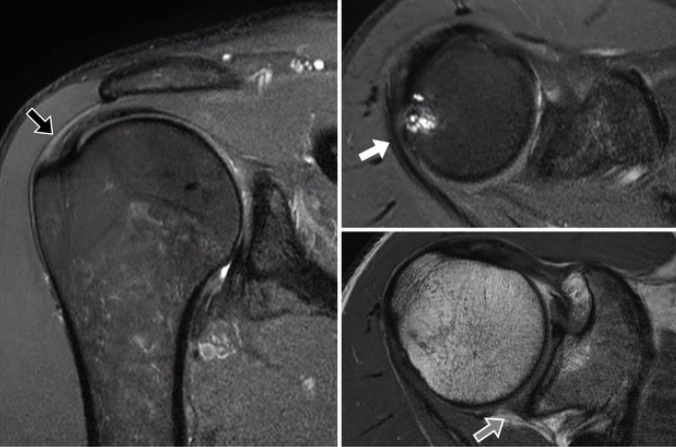

Hội chứng chèn ép khớp vai sau-trên (Posterosuperior impingement of the shoulder)/ Hội chứng chèn ép trong khớp vai (Internal Impingement)